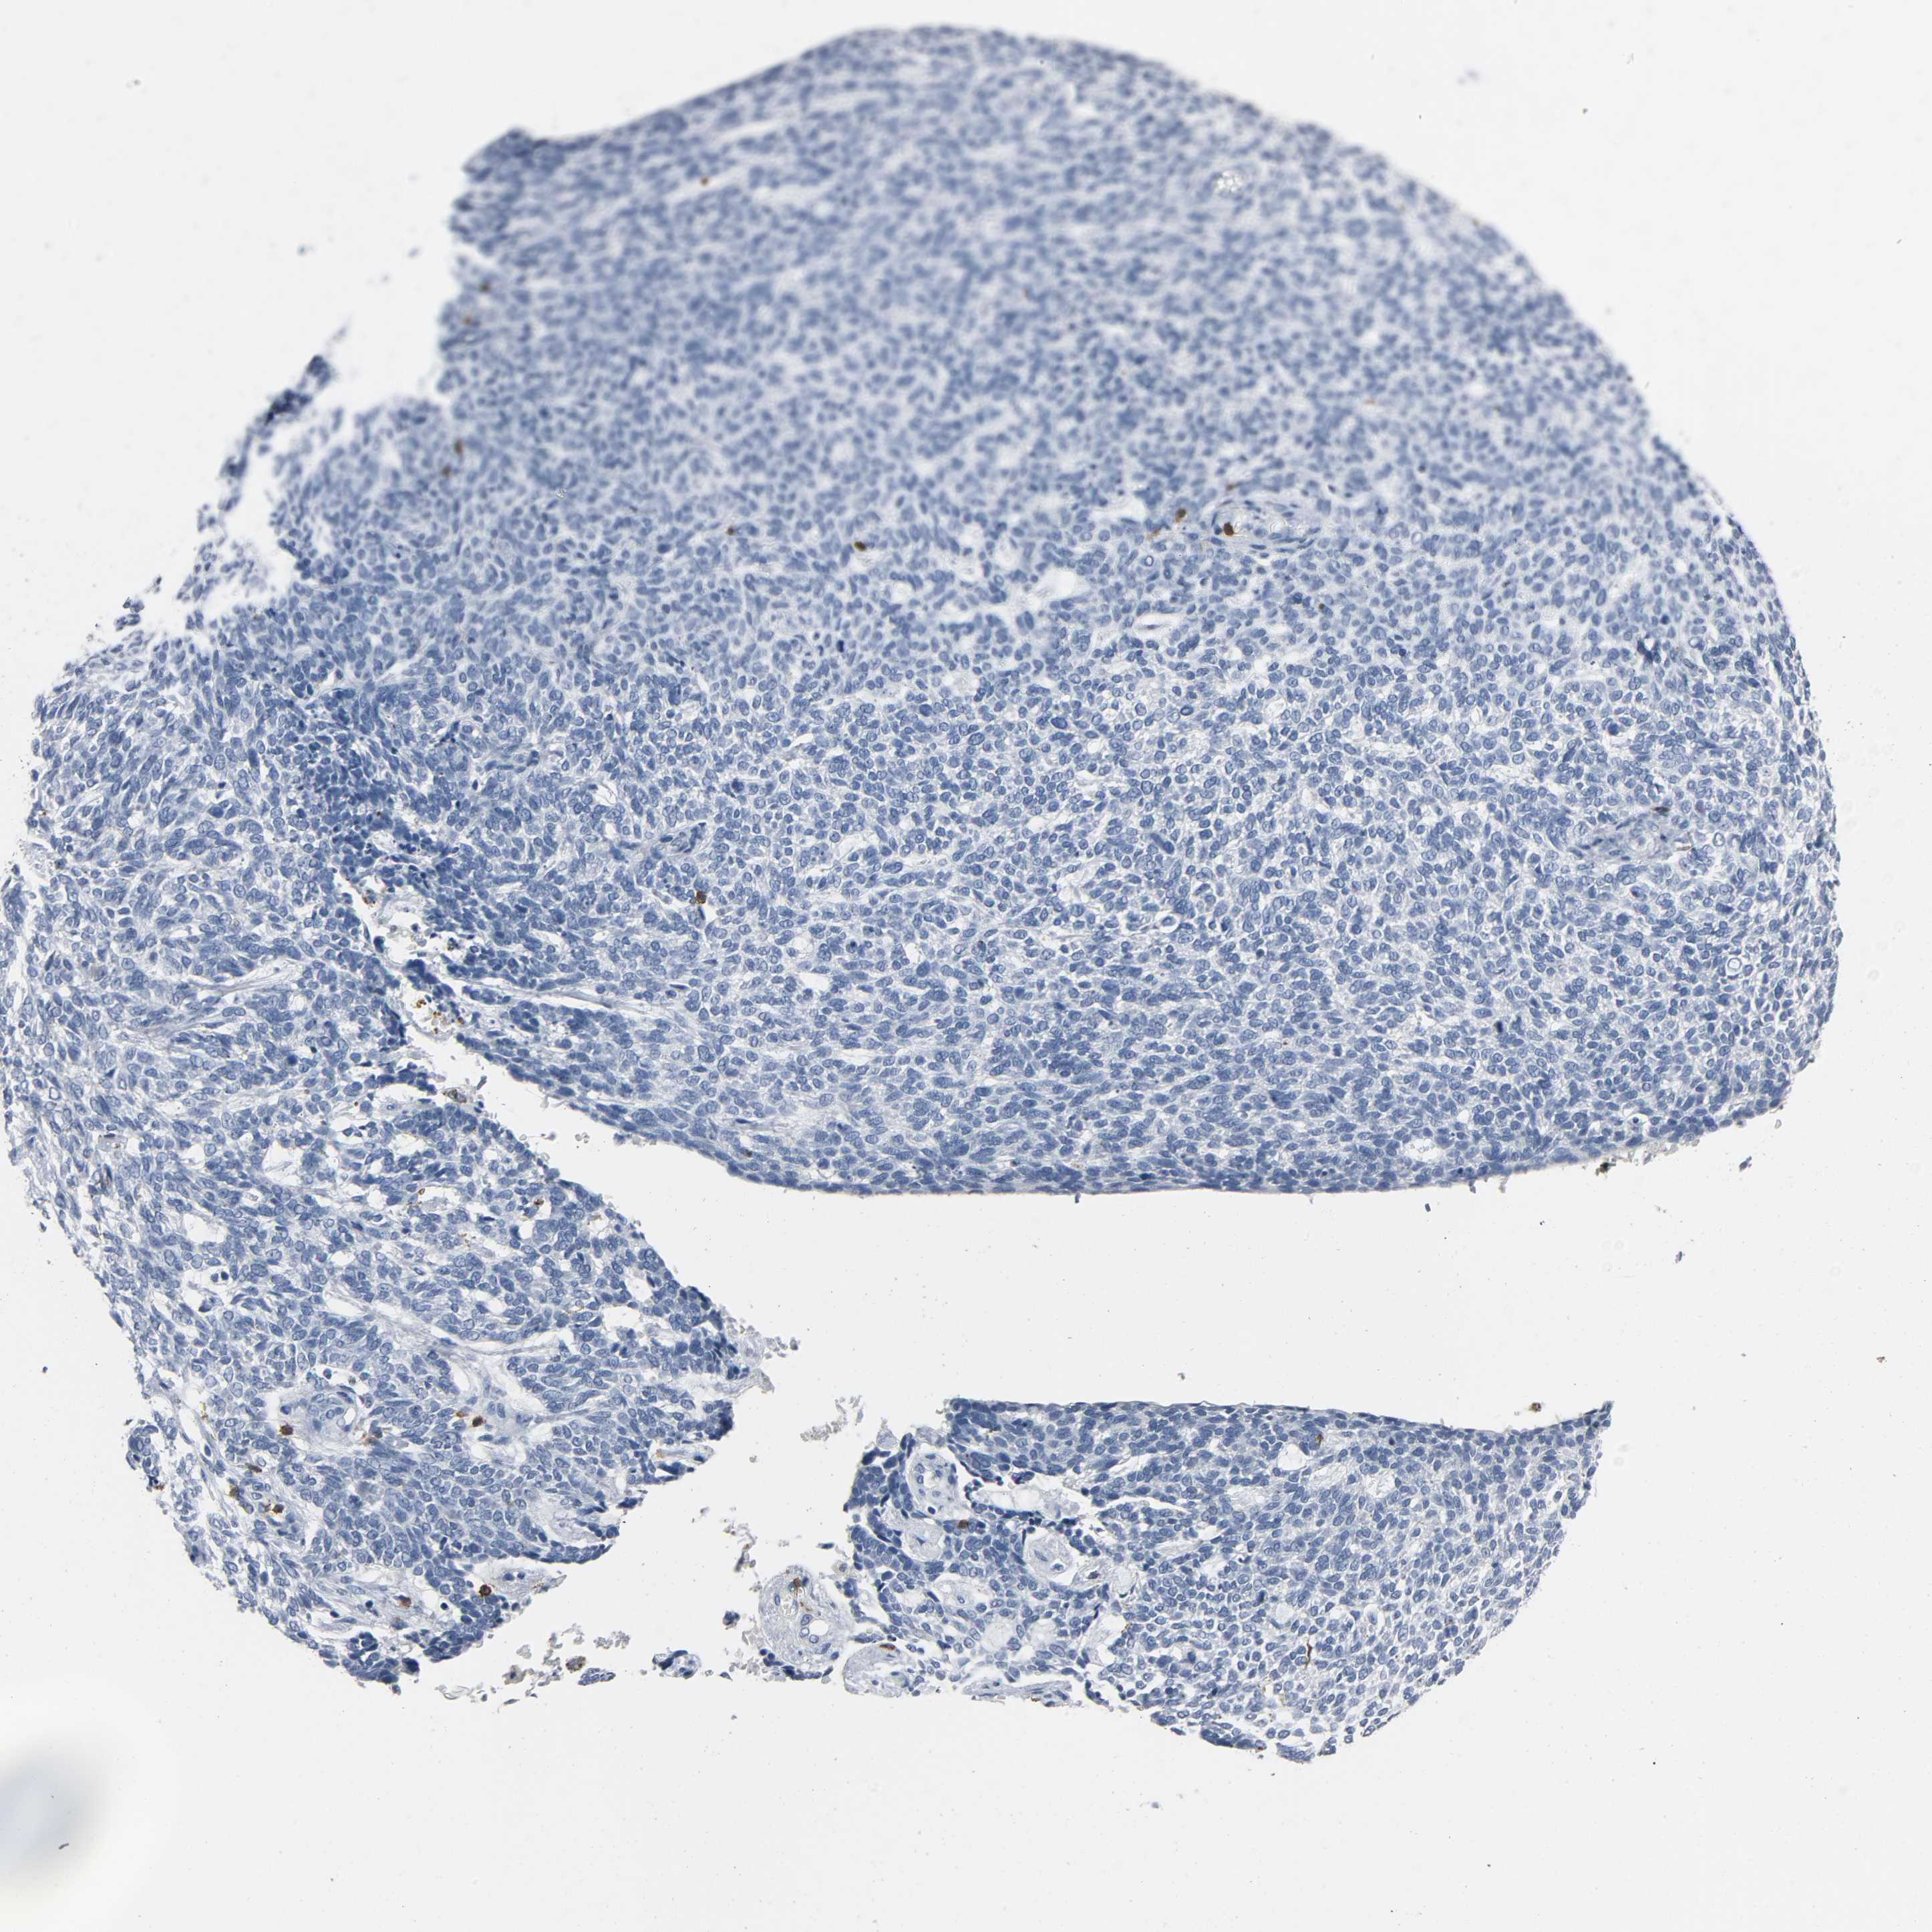

SKIN CANCER - Protein expressioni

A mouse-over function shows sample information and annotation data. Click on an image to view it in a full screen mode. Samples can be filtered based on level of antibody staining by selecting one or several of the following categories: high, medium, low and not detected. The assay and annotation is described here.

Antibody stainingi

Antibody staining in the annotated cell types in the current human tissue is reported as not detected, low, medium, or high, based on conventional immunohistochemistry profiling in selected tissues. This score is based on the combination of the staining intensity and fraction of stained cells.

Each image is clickable and will lead to virtual microscopy that enables deeper exploration of all samples and also displays staining intensity scores, fraction scores and subcellular localization as well as patient and tissue information for each sample.

Antibody HPA003494

Antibody CAB003816

Staining

High

Medium

Low

Not detected

Intensity

Strong

Moderate

Weak

Negative

Quantity

>75%

75%-25%

<25%

None

Location

Nuclear

Cytoplasmic/membranous

Cytoplasmic/membranous,nuclear

Squamous cell carcinoma, NOS

Basal cell carcinoma